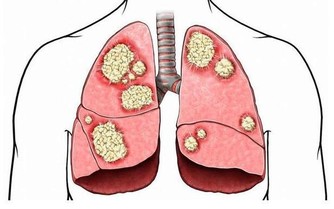

第四,腿肚子酸痛、胸痛、氣短、咳血。這些是危險的腿部血栓形成前兆。久坐之後最易發生,手術之後長時間臥床,也會出現這種症狀。人人都可能得這種病,坐臥時間久了,血液淤積在腿部,腿部出現血栓,小腿肚子腫疼,此時如果突然出現胸痛或者氣短,說明血栓可能已經脫落並通過血液進入肺部。那可是萬分危險,要立刻去醫院。